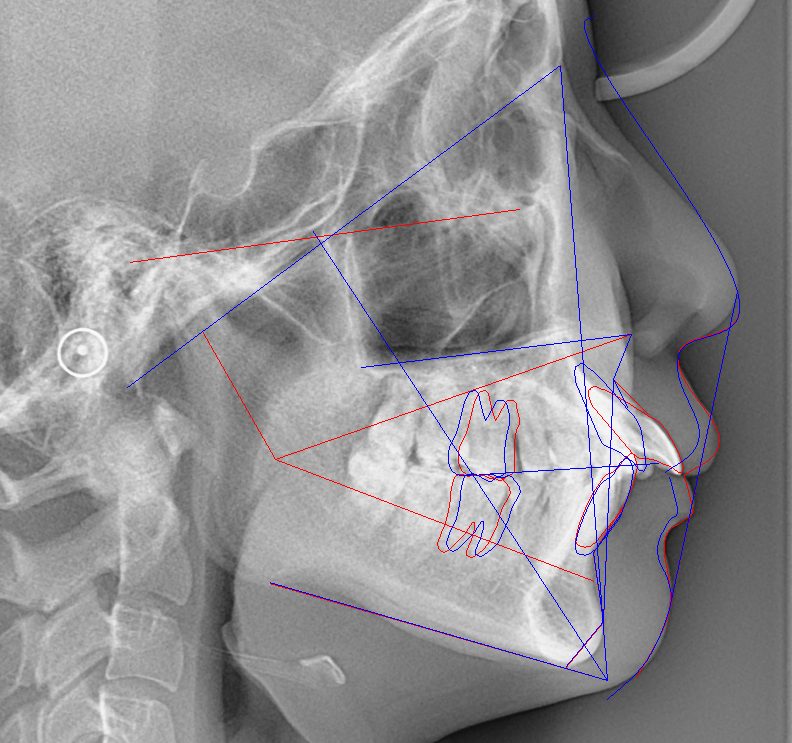

- Eラインは、鼻尖(鼻の先端)とオトガイ(あご先)を結んだ直線です。

矯正治療によるEラインの変化

- 上顎前突(出っ歯)の場合:上唇が後退し、横顔がスッキリ見える

- 上下顎前突の場合:抜歯矯正で上下の唇が後退し、Eラインが整う

- 反対咬合(受け口)の場合:下唇の突出が改善し、調和が取れる

Eラインと唇の動きの関係

- 上顎前歯が1mm後退すると、上唇は約0.5mm後退

- 下顎前歯が1mm後退すると、下唇は約0.6mm後退

- 歯の移動と口唇の移動は「1:0.5〜0.8」の相関あり(個人差あり)

平均的に前歯の移動量の約50%口唇が後退することになります